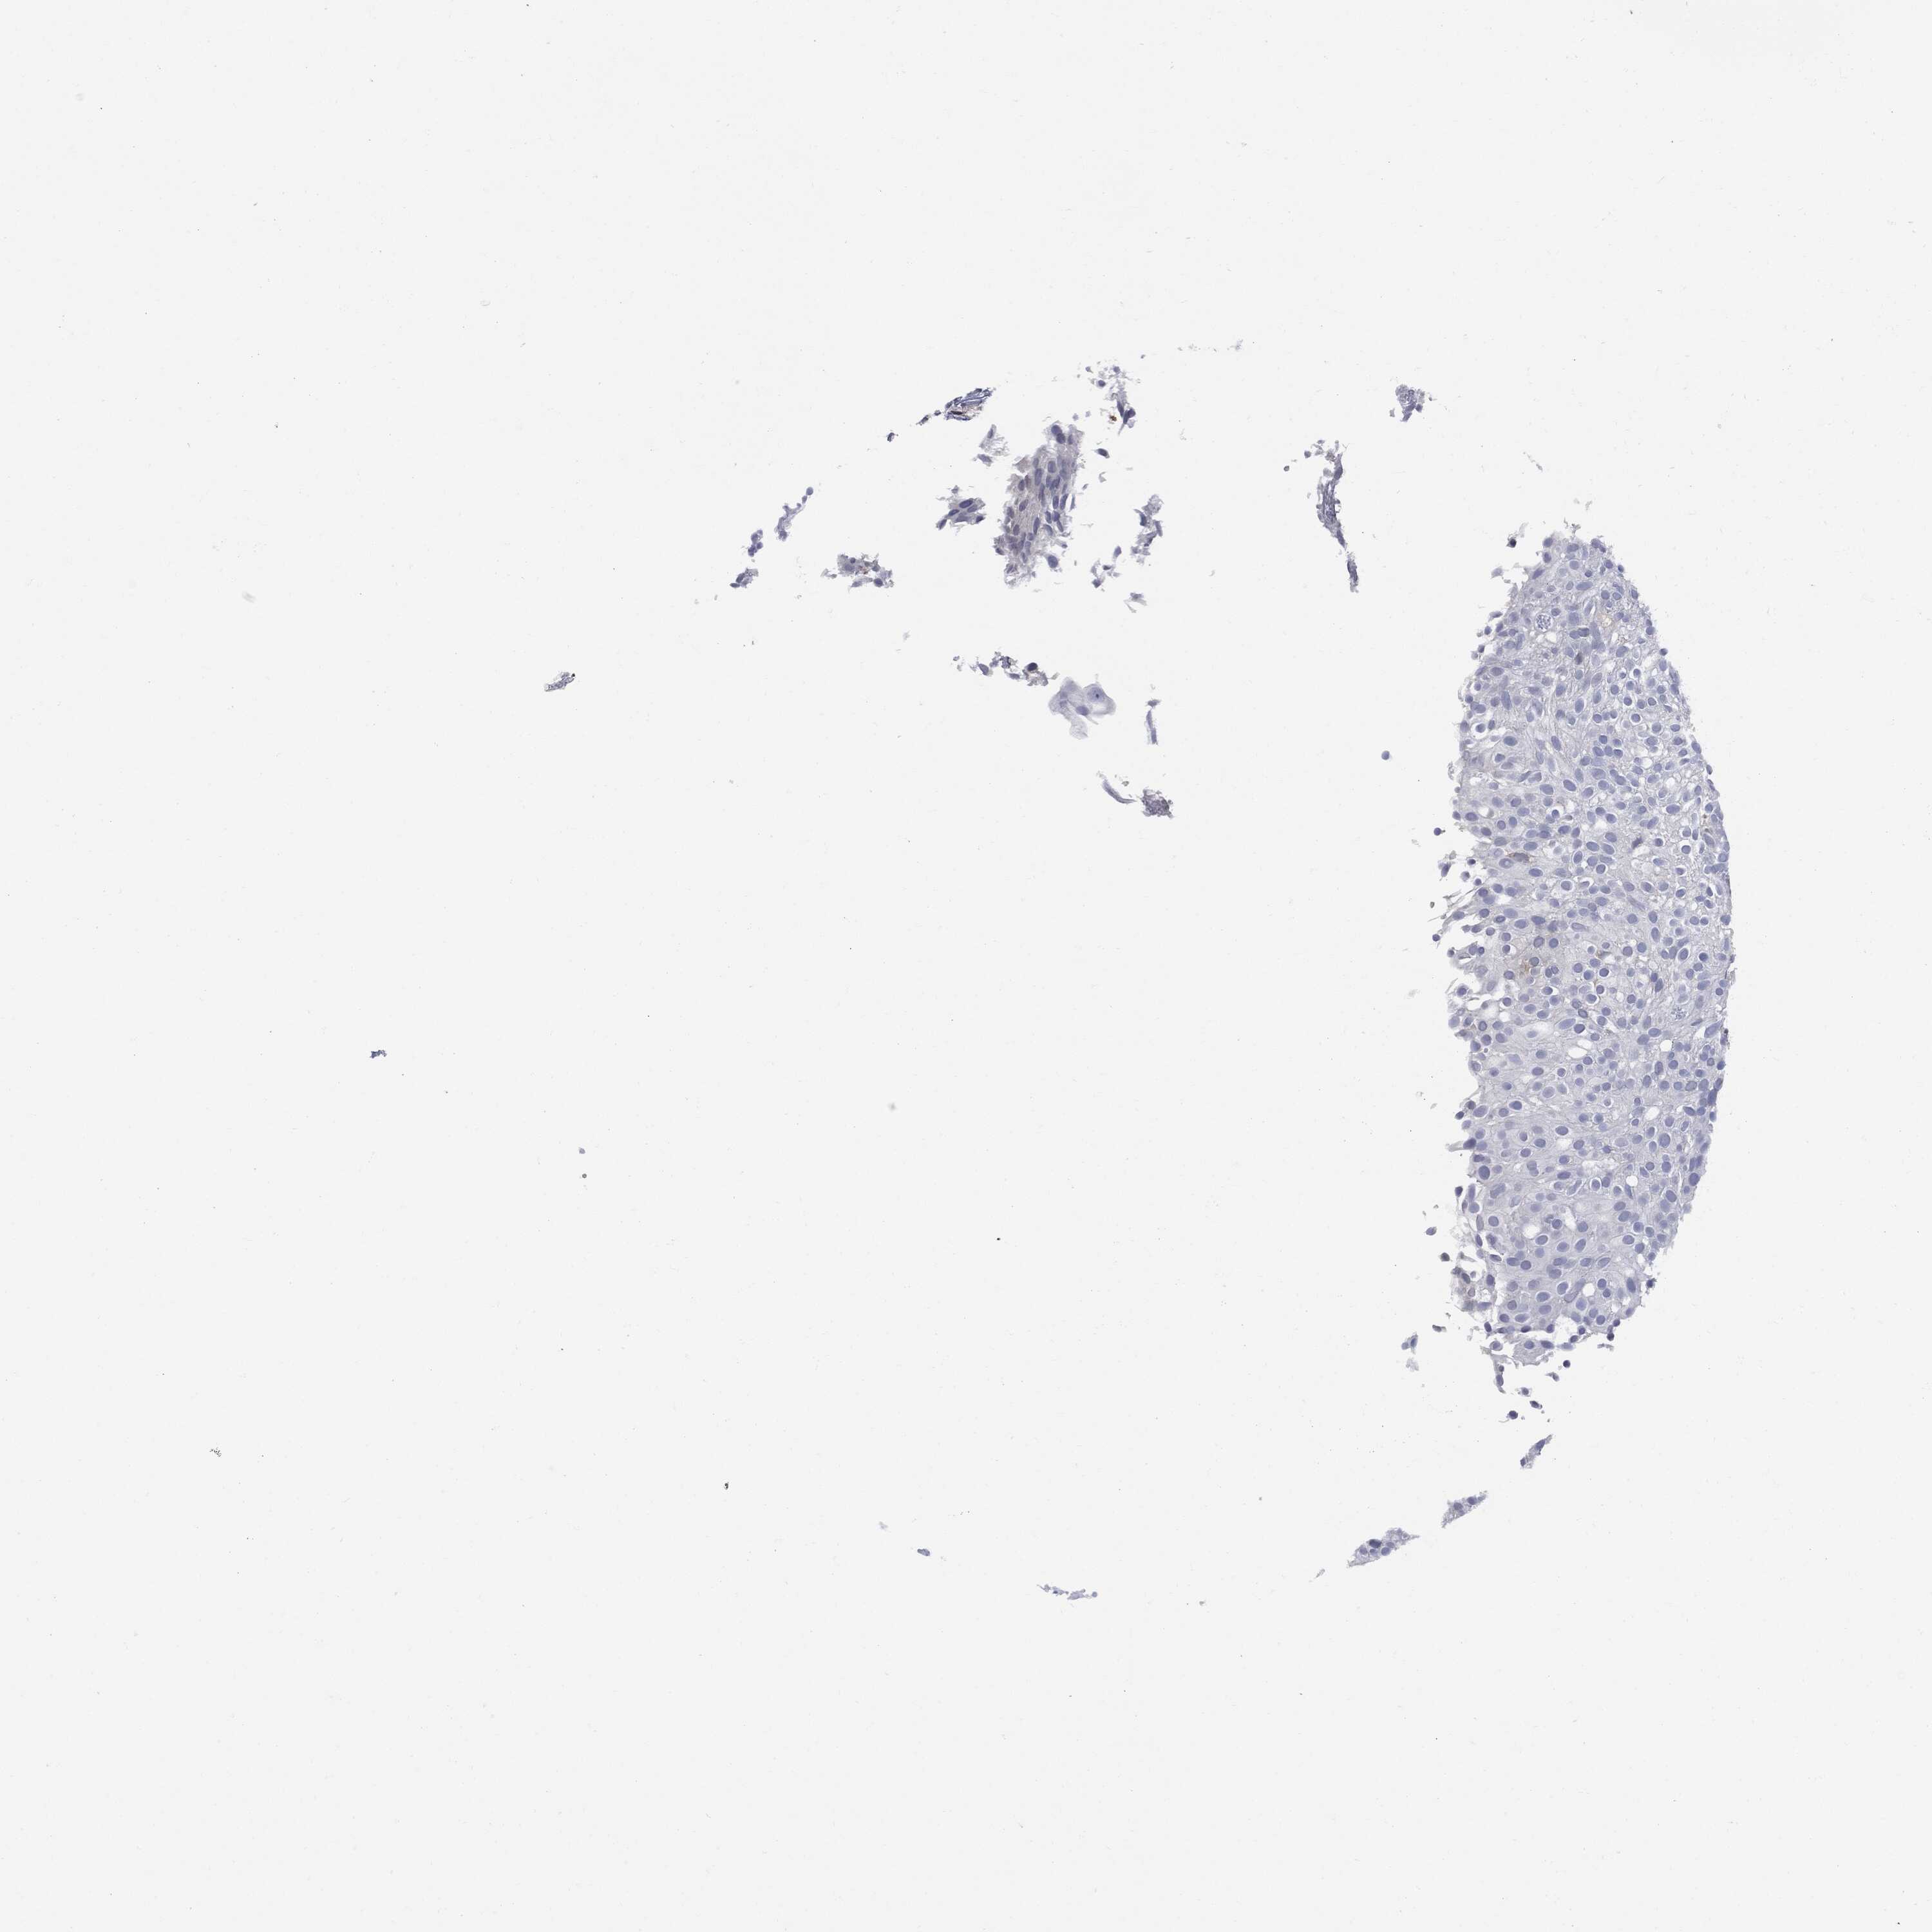

UROTHELIAL CANCER - Protein expressioni

A mouse-over function shows sample information and annotation data. Click on an image to view it in a full screen mode. Samples can be filtered based on level of antibody staining by selecting one or several of the following categories: high, medium, low and not detected. The assay and annotation is described here.

Note that samples used for immunohistochemistry by the Human Protein Atlas do not correspond to samples in the TCGA dataset.

Antibody stainingi

Antibody staining in the annotated cell types in the current human tissue is reported as not detected, low, medium, or high, based on conventional immunohistochemistry profiling in selected tissues. This score is based on the combination of the staining intensity and fraction of stained cells.

Each image is clickable and will lead to virtual microscopy that enables deeper exploration of all samples and also displays staining intensity scores, fraction scores and subcellular localization as well as patient and tissue information for each sample.

Antibody HPA001198

Antibody HPA002028

Antibody CAB016689

Antibody CAB080300

Staining

High

Medium

Low

Not detected

Intensity

Strong

Moderate

Weak

Negative

Quantity

>75%

75%-25%

<25%

None

Location

Nuclear

Cytoplasmic/membranous

Cytoplasmic/membranous,nuclear

Urothelial carcinoma, High grade

Urothelial carcinoma, Low grade

Adenocarcinoma, NOS